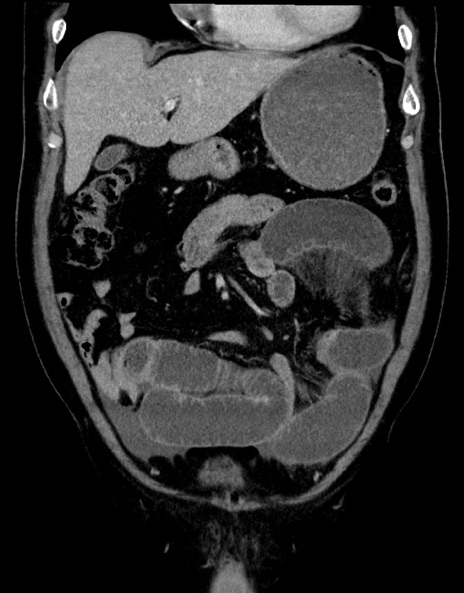

症例15(冠状断像)

【症例】70歳代男性

【主訴】腹痛

【現病歴】今朝から腹痛あり。全体的に痛い。特に左上の方。排ガスが今日はない。冷や汗が出る。

【既往歴】直腸癌術後

【身体所見】左側腹部〜上腹部に圧痛あり。腹膜刺激症状明らかなではない。軽度反跳痛。左下腹部に術後瘢痕あり。

【データ】WBC 7700、CRP 0.02